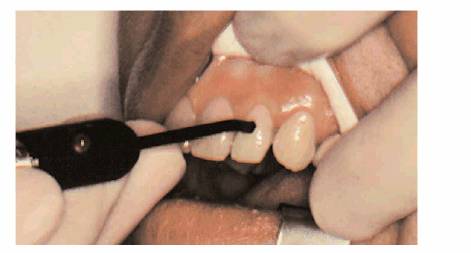

Over the last 25 years, the Analytical Technology Vitality Scanner (Figure 19-13), recently renamed Kerr Vitality

Scanner 2006 (KerrDental,

if root structure is exposed owing to gingival recession, the

"mini-tip" that comes with the Vitality Scanner should be used (Figure 19-15). Unfortunately, this is not a very

accurate method because there is a significant likelihood that the periodontal

ligament would respond to the stimulus, giving the false impression that the

pulp is still vital. The mini-tip, when used in conjunction with a prepared

test cavity or a small opening in a cast crown (Figures 19-16A, and 19-16B), is quite advantageous. This tip

is placed directly through the opening and onto the exposed dentin. Care should

be taken to keep the electrolyte (toothpaste or fluoride gel) from touching the

metal of the casting.

Figure 19-13: Analytical Technology Vitality Scanner Model 2005 (KerrDental).

Figure 19-14: Pulp tester being applied to a dried tooth.

Figure 19-15: Mini-tip for the Vitality Scanner.

Figure 19-16A: Access through porcelain and metal to the dentin.

Figure 19-16B: Mini-tip placed on dentin through prepared cavity.